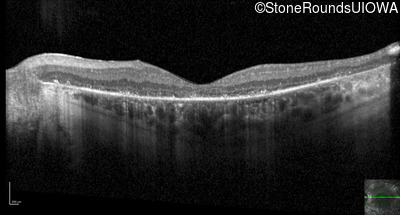

Optical Coherence Tomography - Left - 10/140

Exemplar / OCT Stack

OCT Stack